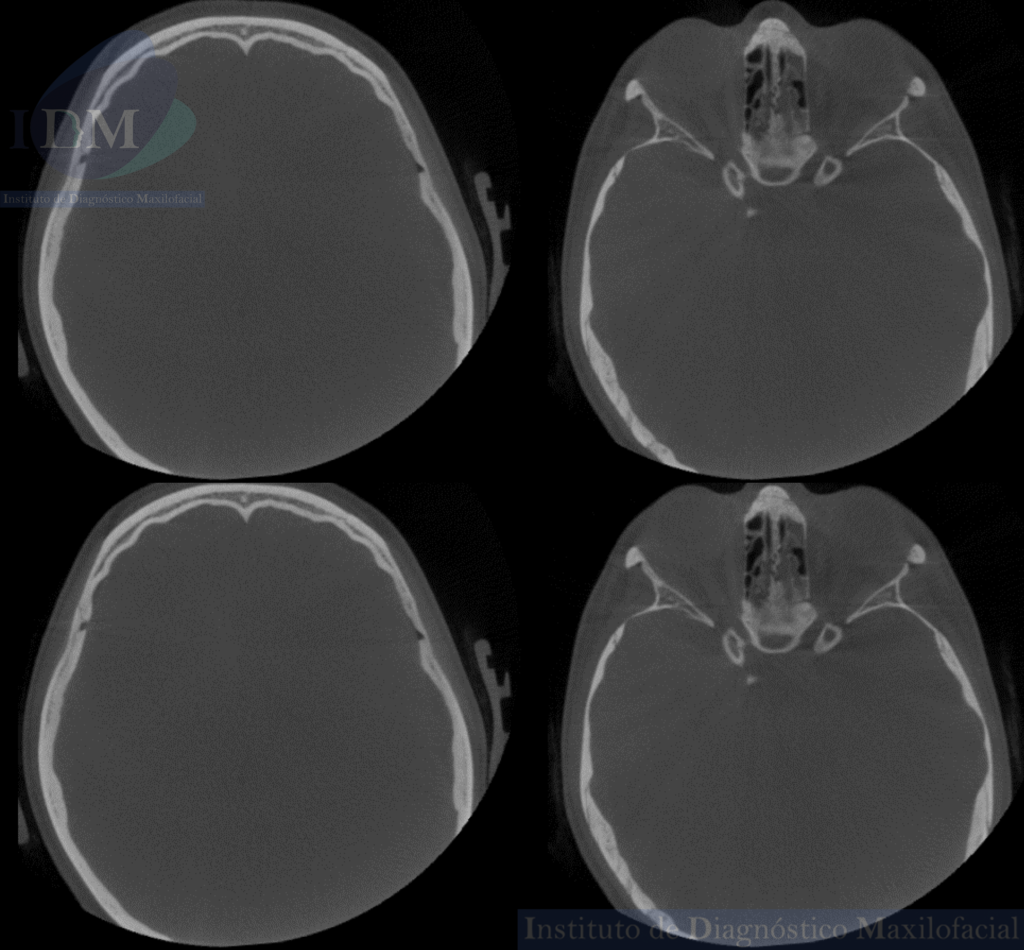

Así mismo en la tomografía volumétrica de haz cónico se evidencia un leve engrosamiento de la mucosa antral de senos paranasales. Siendo lo mas relevante la ausencia de seno esfenoidal en base de cráneo.

CORTES AXIALES